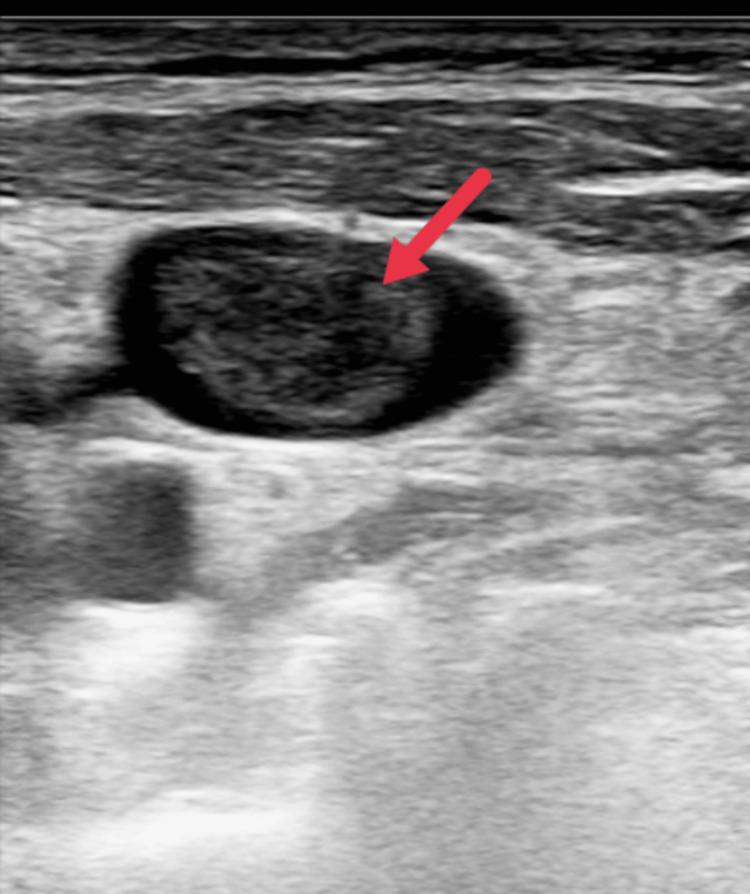

Acute pancreatitis (AP) is an inflammatory condition with varied clinical presentations. Local complications include peripancreatic fluid collection, acute necrotic collection, walled-off necrosis, and pancreatic pseudocyst, but vascular complications like pseudoaneurysm and venous thrombosis are also reported. Patients often experience splanchnic venous thrombosis, which can affect the splenic vein, portal vein, and superior mesenteric vein individually or in combination. Rarely, extra-splanchnic venous thrombosis, including renal vein, superior vena cava, and inferior vena cava thrombosis, has been reported in cases of chronic pancreatitis. The formation of a venous thrombus in acute pancreatitis is multifaceted, with pancreatic inflammation and the immune response mounted by the patient playing a significant role. There is a dearth of medical literature regarding extra-splanchnic venous thrombosis and the use of therapeutic anticoagulation in the successful treatment of the above-mentioned complication. This case report highlights the rare complications that can be seen in cases of acute pancreatitis.

急性胰腺炎(AP)是一种临床表现多样的炎症性疾病。局部并发症包括胰周液体积聚、急性坏死性积聚、包裹性坏死和胰腺假性囊肿,但也有报道称存在诸如假性动脉瘤和静脉血栓形成等血管并发症。患者常发生内脏静脉血栓形成,可单独或联合累及脾静脉、门静脉和肠系膜上静脉。在慢性胰腺炎病例中,罕见报道有包括肾静脉、上腔静脉和下腔静脉血栓形成在内的内脏外静脉血栓形成。急性胰腺炎中静脉血栓的形成是多方面的,胰腺炎症和患者的免疫反应起了重要作用。关于内脏外静脉血栓形成以及使用治疗性抗凝剂成功治疗上述并发症的医学文献较少。本病例报告突出了急性胰腺炎病例中可能出现的罕见并发症。